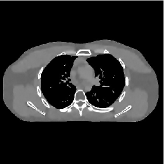

This section compares the reconstruction quality and runtime among the proposed MBIR method, PWLS-ST-, and other three MBIR methods, PWLS-EP, PWLS-DL, and PWLS-ST-. Table I shows that, for both 2D and 3D sparse-view CT reconstructions of the XCAT phantom, the proposed PWLS-ST- model outperforms PWLS-EP and PWLS-ST- in terms of RMSE. In addition, PWLS-ST- using a square transform (of size ) achieves lower RMSE than PWLS-DL using an overcomplete dictionary (of size ) for 2D sparse-view reconstructions. Fig. 3(a) and Fig. 4 show the reconstructed images for 2D and 3D phantom experiments, with different reconstruction models and different number of views. (See the corresponding error maps in the supplement.) The proposed PWLS-ST- consistently gives more accurate image reconstructions compared to other MBIR methods. Specifically, PWLS-ST- has smaller errors in the heart region (see zoom-ins in Fig. 3(a)) of 2D reconstructions than PWLS-DL and PWLS-ST-. In addition, compared to PWLS-ST-, PWLS-DL and PWLS-ST- have some ringing artifacts around the edges with high transition, e.g., edges between air and soft tissues. (See a comparison of profiles of PWLS-ST- and PWLS-ST- in the supplement.) In particular, PWLS-ST- and PWLS-DL give more visible ringing artifacts for 2D reconstruction from fewer views, and PWLS-ST- has these ringing artifacts for 3D reconstructions regardless of the number of views (see zoom-ins in Fig. 4). Table II reports runtimes of different MBIR methods in reconstructing the -views XCAT phantom scan. (FBPConvNet is a non-MBIR method and its runtime for processing a image is approximately one second with a TITAN Xp GPU.) While providing better reconstruction quality, the proposed Algorithm 1 of PWLS-ST- has shorter runtime compared to the algorithms of PWLS-DL and PWLS-ST- in Section III-A. Similar to the PWLS-EP algorithm, the reconstruction time of the PWLS-DL, PWLS-ST-, and PWLS-ST- algorithms can be further reduced by using ordered subsets [51].

Fig. 3(b) shows that when tested on the clinical scan data, the proposed PWLS-ST- method improves reconstruction quality in terms of noise and artifacts removal (e.g., see zoom-ins for soft-issue regions), and edge preservation (e.g., see zoom-ins for bone regions), compared to PWLS-EP and PWLS-ST-. Compared to PWLS-DL, PWLS-ST- achieves comparable image quality, but requires less computational complexity.

The benefit of the proposed PWLS-ST- over PWLS-ST- can be explained when there exist some outliers for some : in (12) gives equal emphasis to all sparse codes – from small to large coefficients that generally correspond to edges in low- and high-contrast regions, respectively – in estimating ; however, PWLS-ST- adjusts to mainly minimize the outliers, i.e., it may not pay enough attention to reconstruct regions with small coefficients. The histogram results in Fig. 1 reveal model mismatch of PWLS-ST- over the iterations. Fig. 3, Fig. 4, and Table I show that PWLS-ST- can moderate model mismatch, and provides more accurate reconstruction than PWLS-ST-.

![]() |

| (a) 2D fan-beam CT experiments |